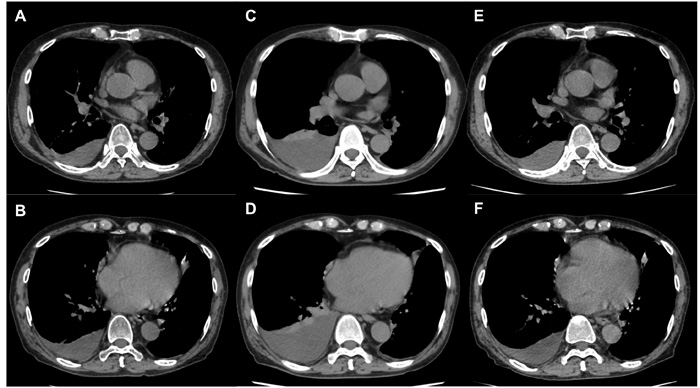

Three months after the final administration of first-line chemotherapy, progressive disease was detected as an increase in pleural effusion on a CT scan and pleural fluorodeoxyglucose uptake. Despite administering ramucirumab (10 mg/kg, Day 1) plus docetaxel (60 mg/m2, Day 1) as second-line chemotherapy, a CT scan revealed that, after 2 cycles, the pulmonary nodules were unchanged, but the pleural effusion had increased. Therefore, the MPE was considered progressive. Serum VEGF-A levels increased from 143.0 pg/mL before second-line chemotherapy to 511.0 pg/mL after second-line chemotherapy. This high level of serum VEGF-A was maintained after 2 treatment cycles.

Pleurodesis was not considered indispensable at this point, because the patient did not have severe symptoms of MPE after administration of ramucirumab plus docetaxel combination therapy. Subsequently, bevacizumab (15 mg/kg, Day 1) plus docetaxel (60 mg/m2, Day 1) was administered for progressive MPE. After 2 cycles, a CT scan revealed a reduction in the pleural effusion with the pulmonary nodule remaining stable. Moreover, the patient’s serum VEGF-A levels had decreased from 549.0 pg/mL before administration to <15.6 pg/mL on Day 3 of the first treatment course. A response was maintained for 4 months after the administration of bevacizumab plus docetaxel combination therapy and has continued to be maintained.

Figure 1: Changes in MPE with treatment. MPE A., B. at initiation of ramucirumab plus docetaxel and C., D. after 2 cycles of ramucirumab plus docetaxel; MPE increased and progressive disease was confirmed. MPE decreased after 2 cycles of bevacizumab plus docetaxel E., F.